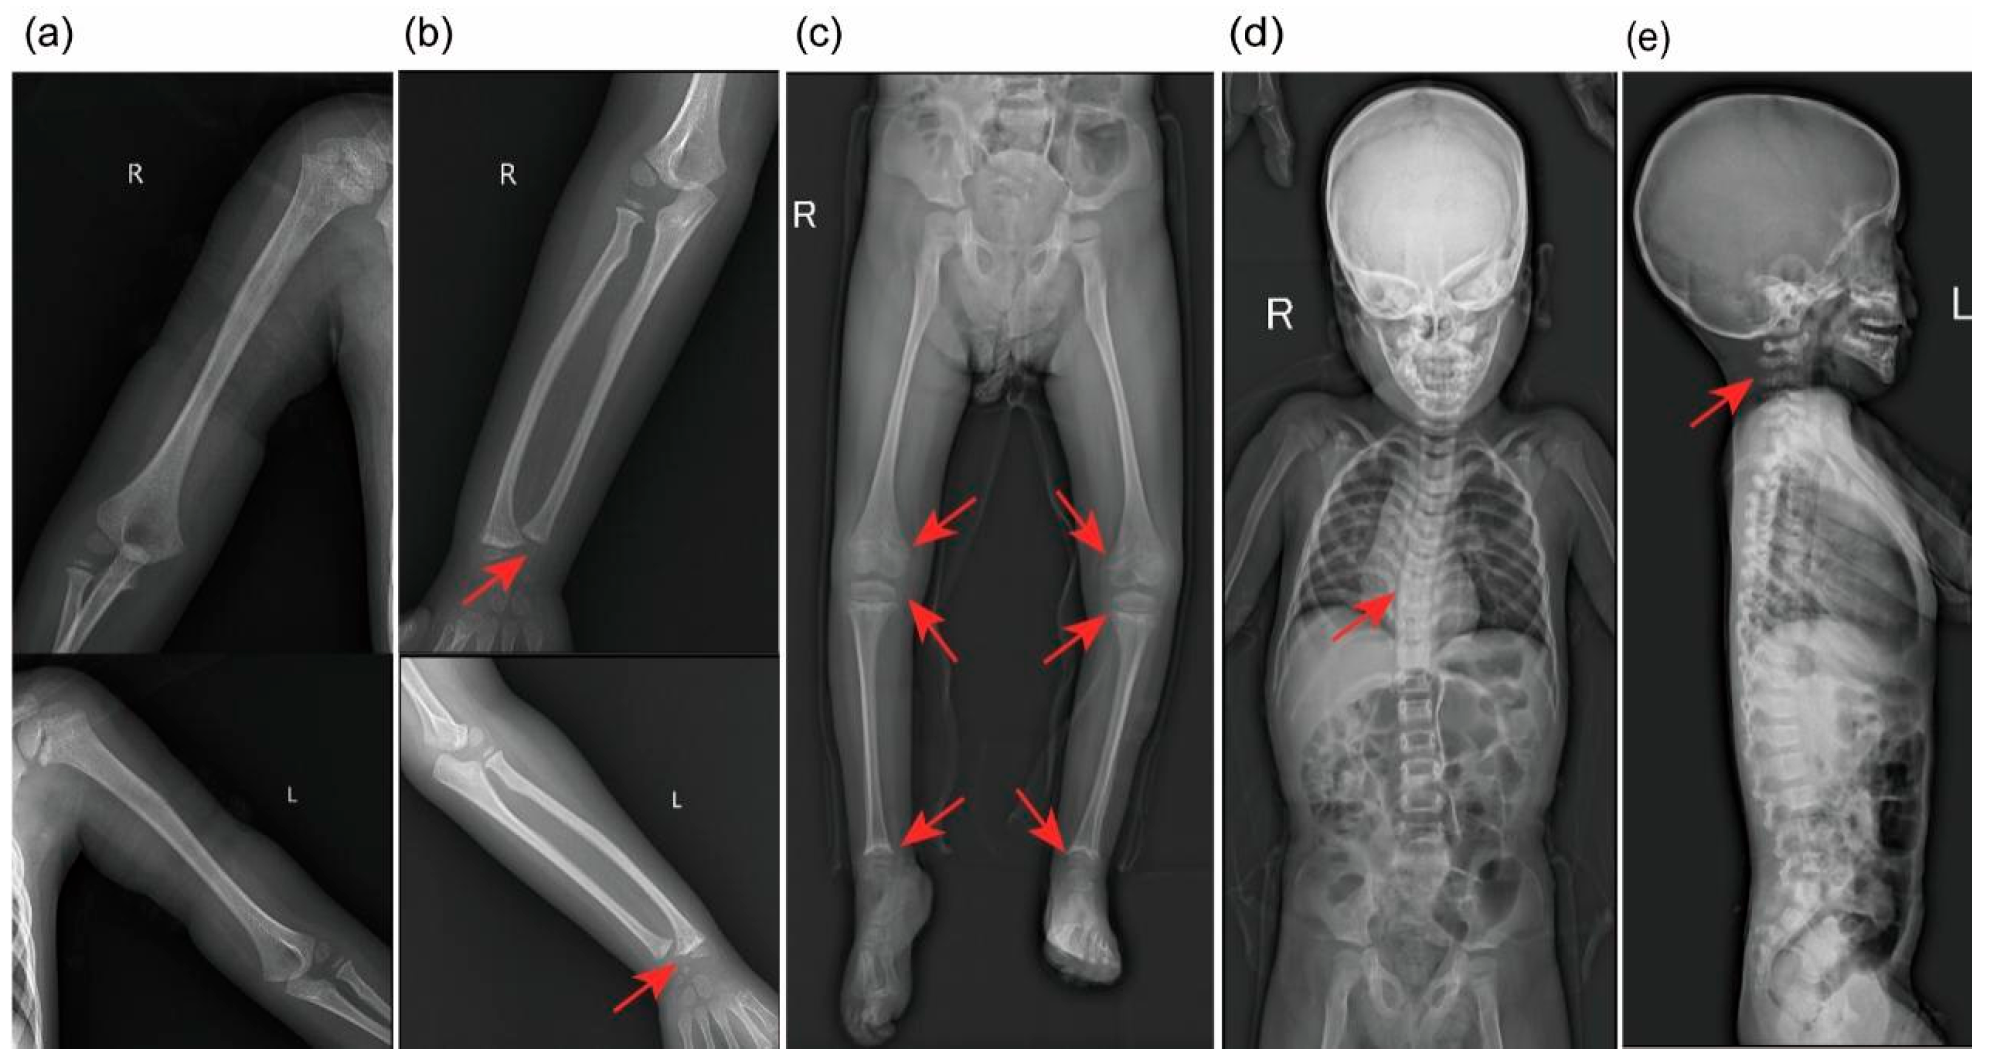

3.3. Imaging

| Skeletal | Birth | Barrel-shaped chest, scoliosis, varus deformities, and dorsiflexion of the first metatarsophalangeal joints in both feet; metaphyseal lesions | None |